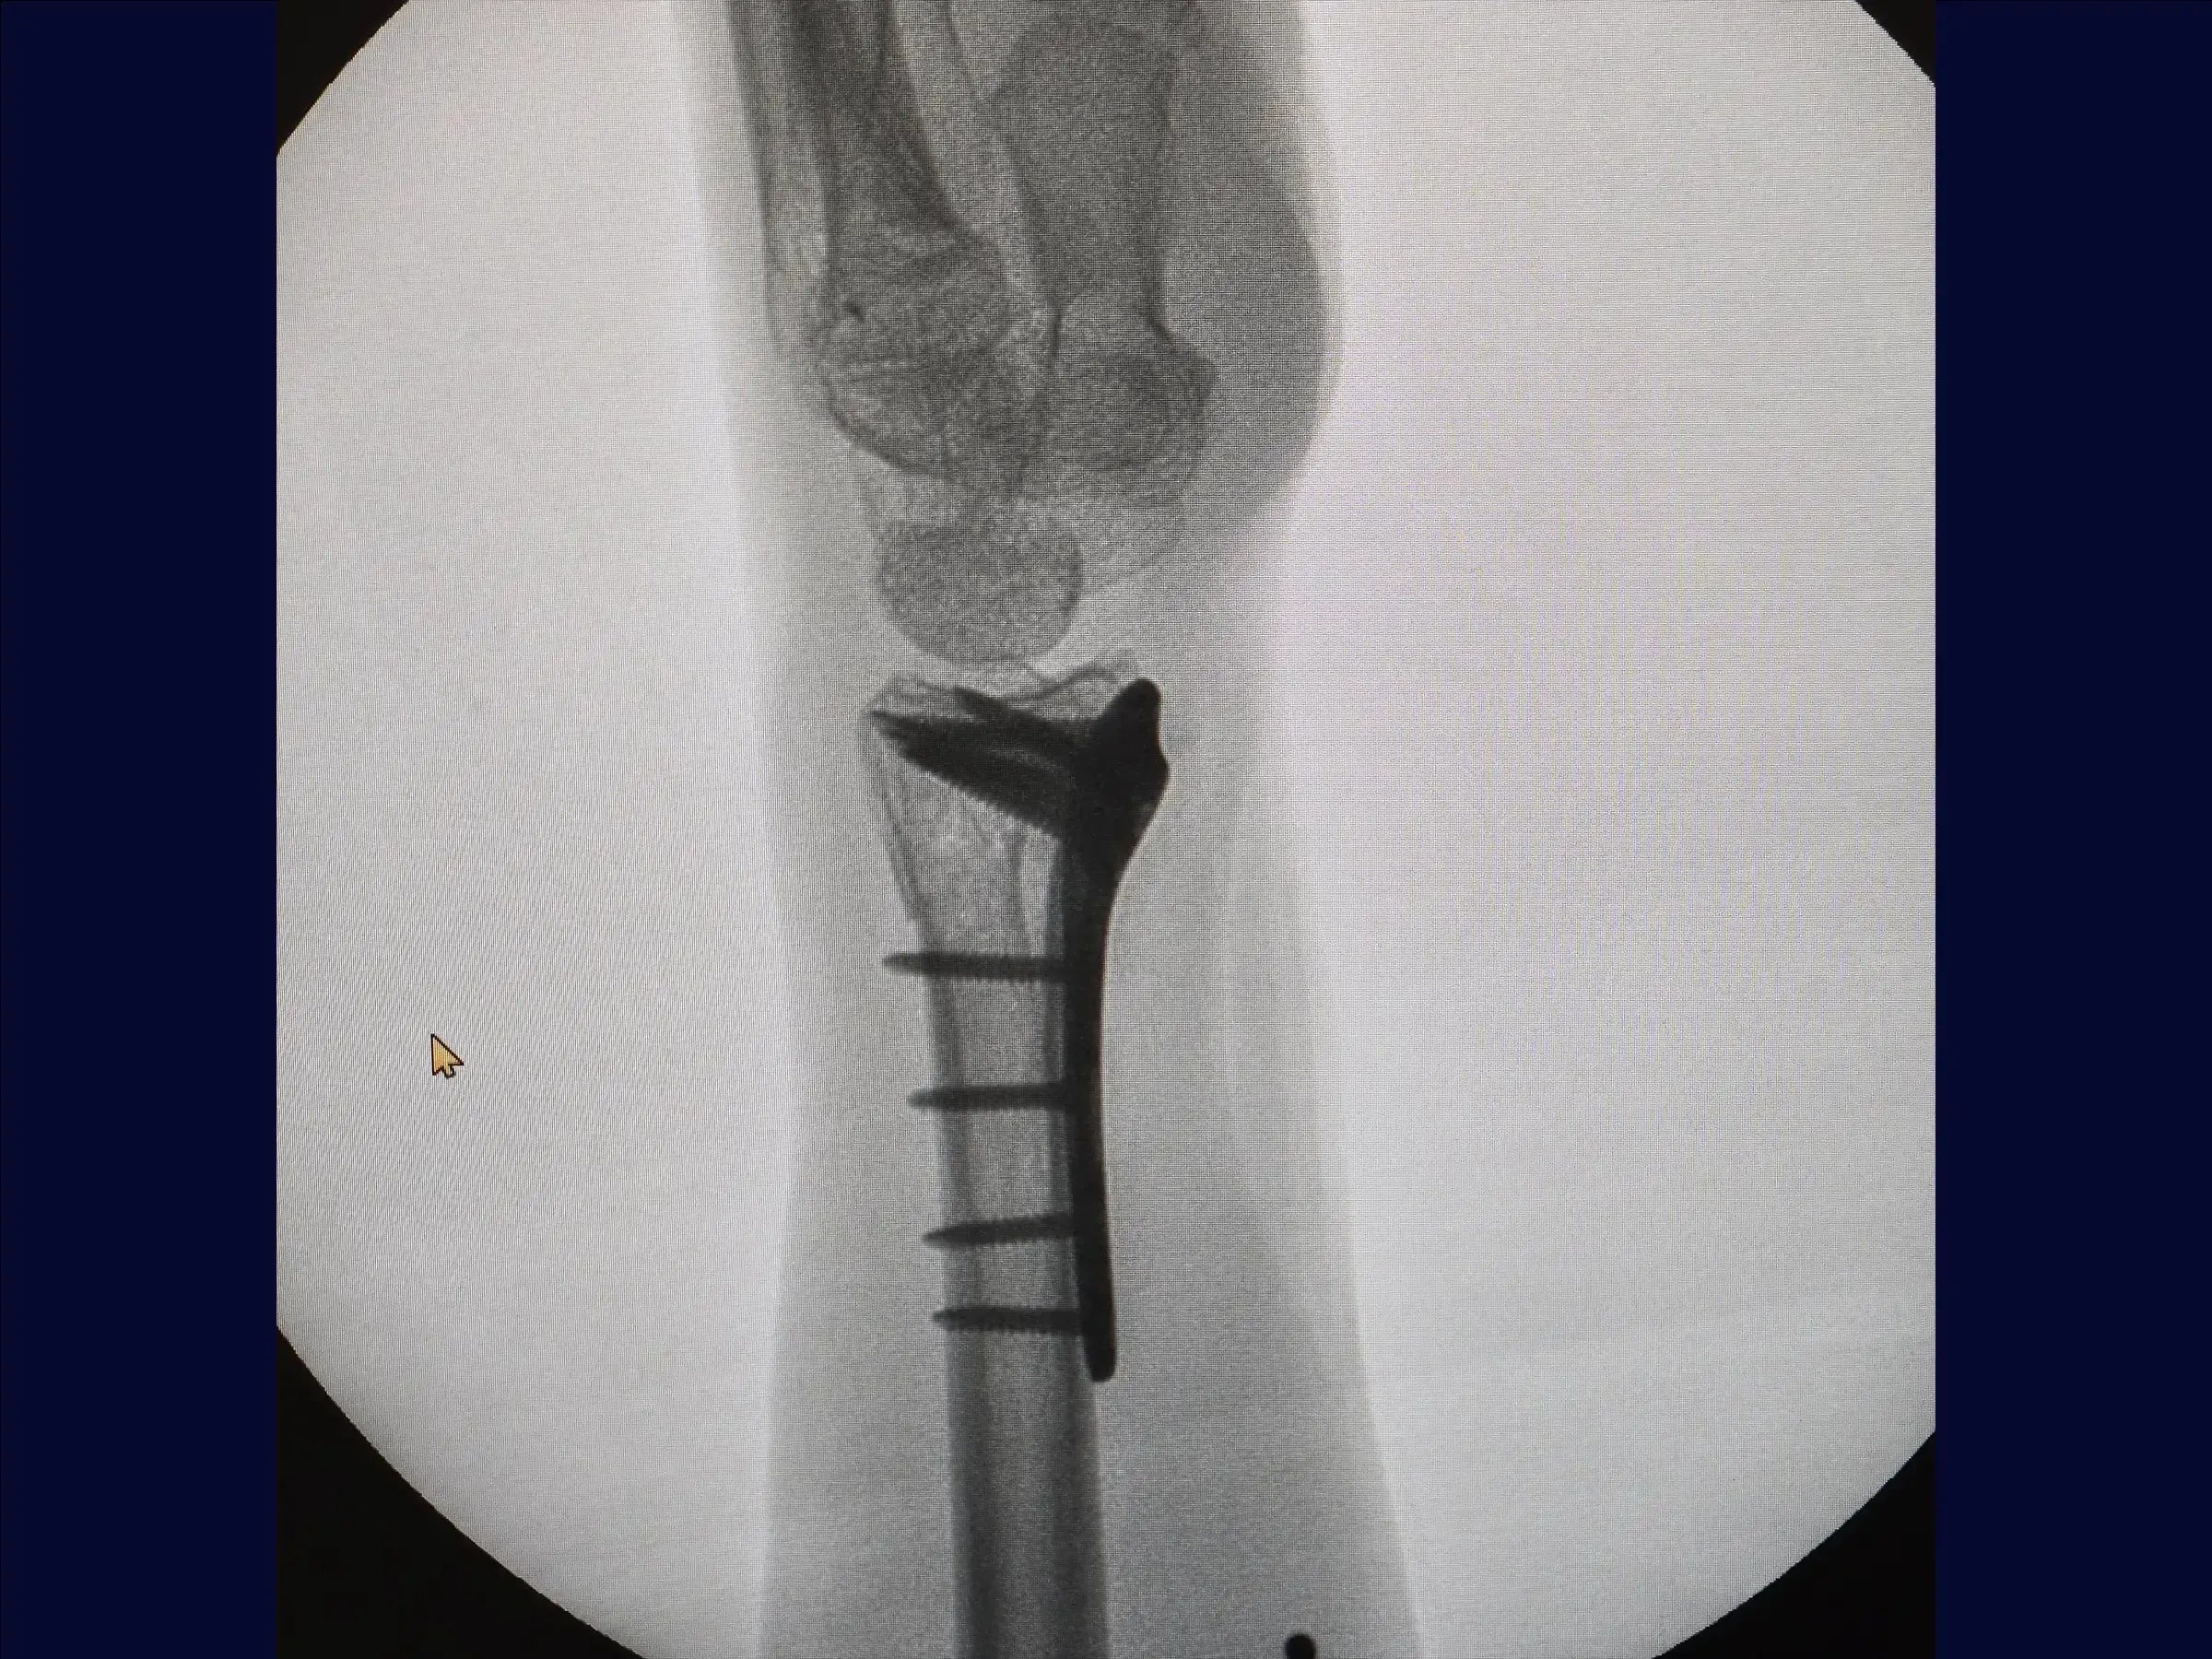

Fractura multifragmentaria del radio distal (abordaje volar)

Domine el tratamiento quirúrgico de las fracturas multifragmentarias del tercio distal del radio con esta formación centrada en el abordaje volar. El procedimiento busca restaurar la longitud radial y la congruencia articular mediante una combinación de tracción manual, fijación percutánea provisional y una estrategia de fijación con placa volar y tornillos de diferentes longitudes para estabilizar los múltiples fragmentos, incluido el componente dorsal, sin necesidad de un abordaje dorsal adicional.

- Preparación y fijación volar: Se reemplaza el retractor, se limpian los vértices de la fractura y se inserta la placa, respetando el límite articular. Se comienza con un tornillo cortical en el orificio oval para compresión. Se utilizan tornillos cortos para fijar el fragmento volar y, con maniobras digitales, tornillos largos estabilizan la superficie dorsal sin necesidad de otro acceso. Los tornillos cortos se reemplazan por tornillos largos (18-20 mm), incluyendo la estiloides, completando la osteosíntesis en los orificios restantes.

- Cierre y resultados finales: Se sutura el pronador cuadrado en línea recta. La reducción es satisfactoria, con una anatomía del radio prácticamente normal. Se realiza un cierre cutáneo para obtener un resultado satisfactorio.